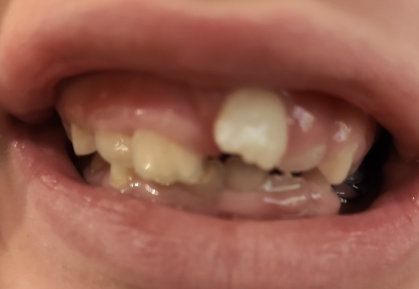

У моего ребенка выпали зубы передние верхние уже как 2,5 года. Новые зубы не растут. Один зуб вылез и тот поперек и на половину, и остановился в росте.

Что делать с зубом, который вылез неправильно? Он может развернуться сам со временем или нет? Что делать?

Маловероятно самостоятельное исправление зубов.

Рекомендуем вам обратиться к стоматологу-ортодонту. В ряде случаев встречается анкилоз зуба или что либо, блокирующее прорезывание. Причину лучше искать на КЛКТ.